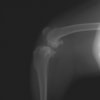

術前左後肢側面像

術後左後肢側面像

本症例は、走った後に左後肢を挙上していることを主訴に来院されました。触診時に左膝関節のクリック音を聴取、レントゲン検査にて左脛骨の前方変位が認められました。術中に、前十字靱帯の断裂及び内側半月板の損傷、内側の軟部組織の顕著な腫脹を確認。半月板切除、TPLOを実施しました。周囲組織への炎症の波及もあったため回復に時間を要しておりますが、徐々に跛行頻度は減少傾向にあり、現在も経過観察中です。術前に約29°あったTPAは術後に約10°まで矯正されました。

手術前後のTPA(脛骨高平部の角度)を測定しています。

約29°から約10°へ矯正されています。